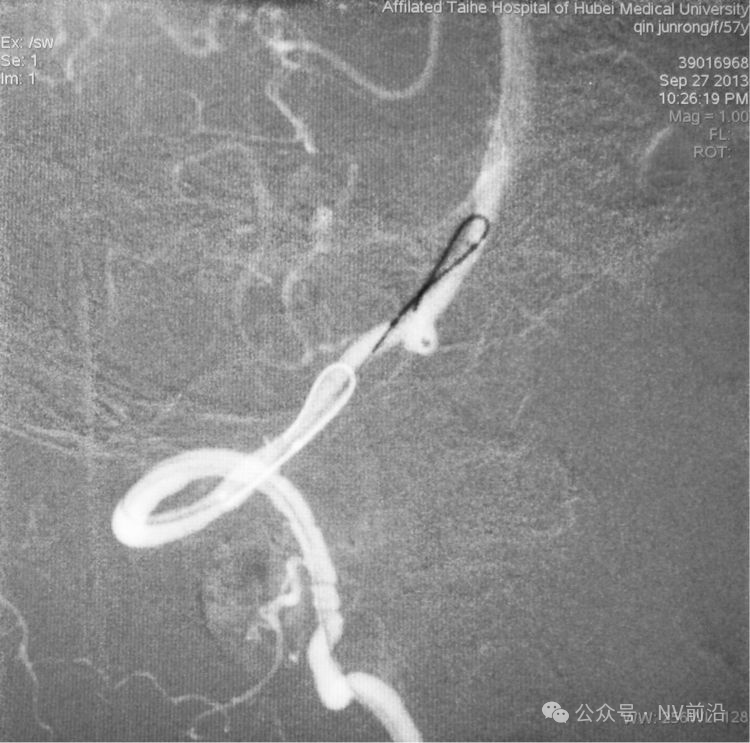

跨瘤颈释放Solitaire 4×20支架(蓝线),压住微导管(红线),在支架保护下经返折的微导管送入弹簧圈填塞瘤腔。

依次送入QC-2-4-3D,2-3-Helix,1.5-2-Helix,1.5-2-Helix四枚弹簧圈,最后一枚弹簧圈将管头(箭头)顶出瘤腔。

将Traxcess 14微导丝送入微导管,稍向远心端送微导管,使管头远离动脉瘤,再缓慢撤离。

解脱第一枚Solitaire 4×20支架后,套叠置入第二枚Solitaire 4×20支架,置入两枚支架的原因是考虑该瘤是夹层动脉瘤,多支架能够强化血流导向作用,有利于夹层愈合。